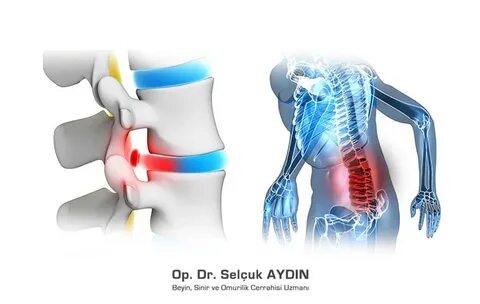

Bel ağrıları, yetişkin popülasyonda hekimlere en sık başvuru nedeni olarak ilk sırada yer alıyor. Toplumumuzda her 10 kişiden 8’i yaşamlarının herhangi bir döneminde bel ağrısı sorunuyla karşılaşıyor. Yaygın inanışın aksine, bel ağrılarının çok az bir kısmı ‘fıtık’ nedenli oluyor. Beyin ve Sinir Cerrahisi Uzmanı Prof. Dr. Ziya Akar, toplumda bel fıtığı hakkında doğru sanılan hatalı bilgileri anlattı; önemli öneriler ve uyarılarda bulundu.